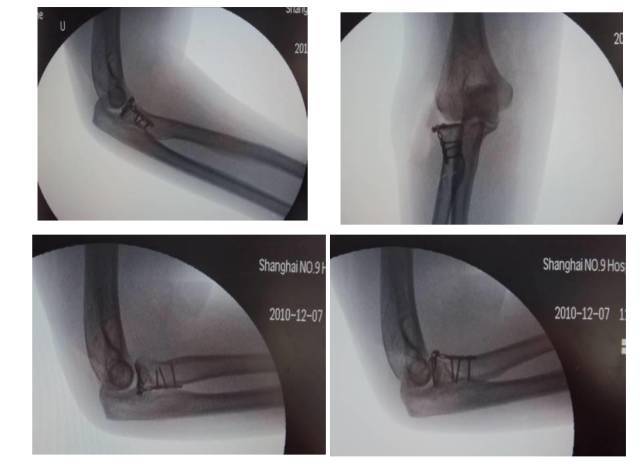

冠突是一个非常重要的稳定结构

• Ⅰ型和Ⅱ型单纯冠状突骨折,发生后方半脱位的风险很小,允许早期活动

• 即使单纯Ⅲ型骨折,在很小的生理应力下也有可能发生后方半脱位,特别是在屈肘60°~105°,支持对Ⅲ型损伤ORIF